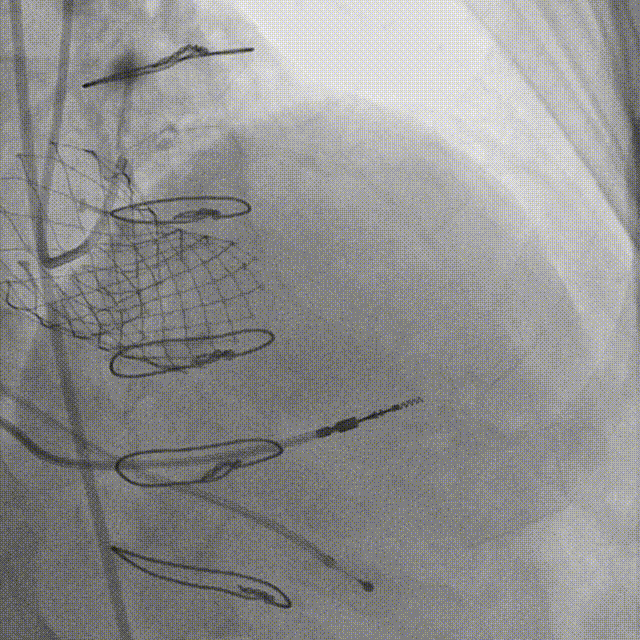

7.术后即刻超声

术中即刻超声